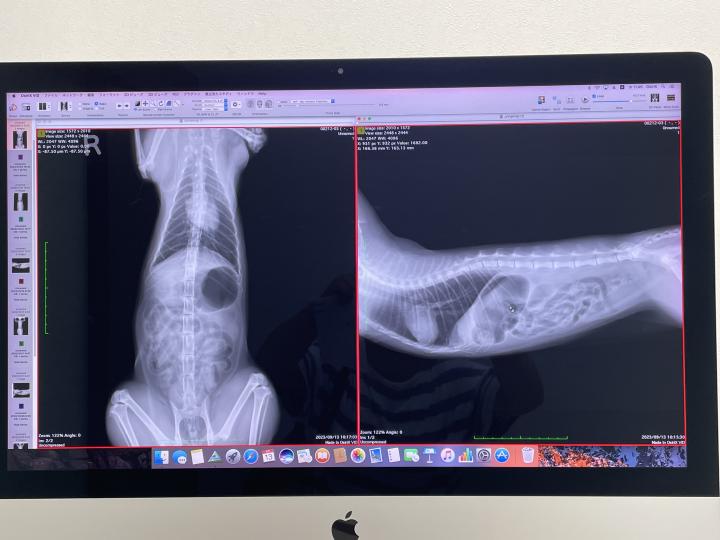

レントゲンで見ると、胃と腸がガスでパンパン

エコーで見ると、胃と腸の境当たりのリンパ節に炎症アリ。

『リンパ腫疑い』

との所見。